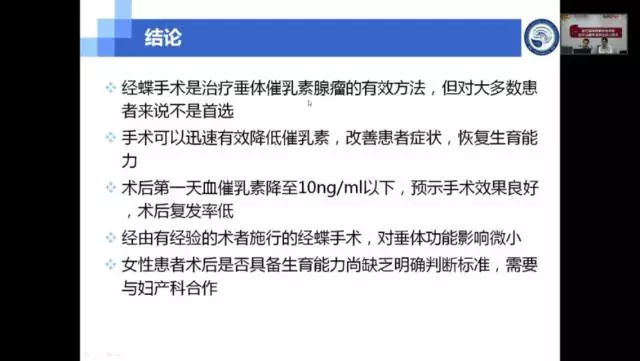

2017年10月19日由复旦大学附属华山医院王镛斐教授和寿雪飞教授主讲的“垂体泌乳素瘤的外科治疗”完美落幕,此次活动是爱惜康神外微课堂即华山神外同学会线上微课的第三期,后续我们也还会陆续开展系列活动,敬请关注。现在活动回顾已上线,诚邀您点击下方链接观看。